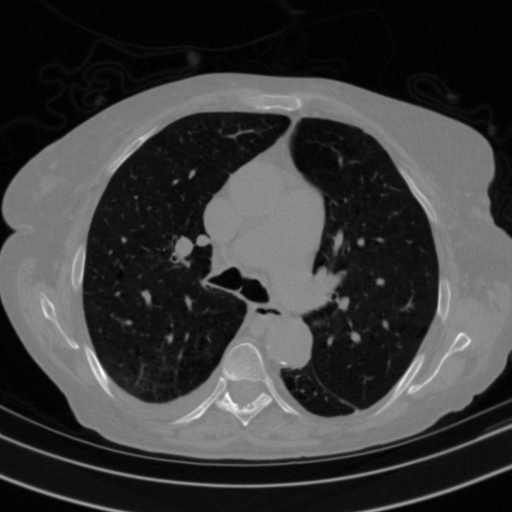

Targeted Slice 70 - Lung Window Analysis (Generated vs Real Venous)

0.598

Lung SSIM

162.3

Lung RMSE

72.3

Lung MAE

Average Lung Window Metrics Across All Slices (153 slices) - Generated vs Real Venous

0.579

Lung SSIM (Avg)

146.5

Lung RMSE (Avg)

66.3

Lung MAE (Avg)

Original NATIVE CT scan (input)

Lung window (WL -600, WW 1500 β†’ Low βˆ’1350, High +150)